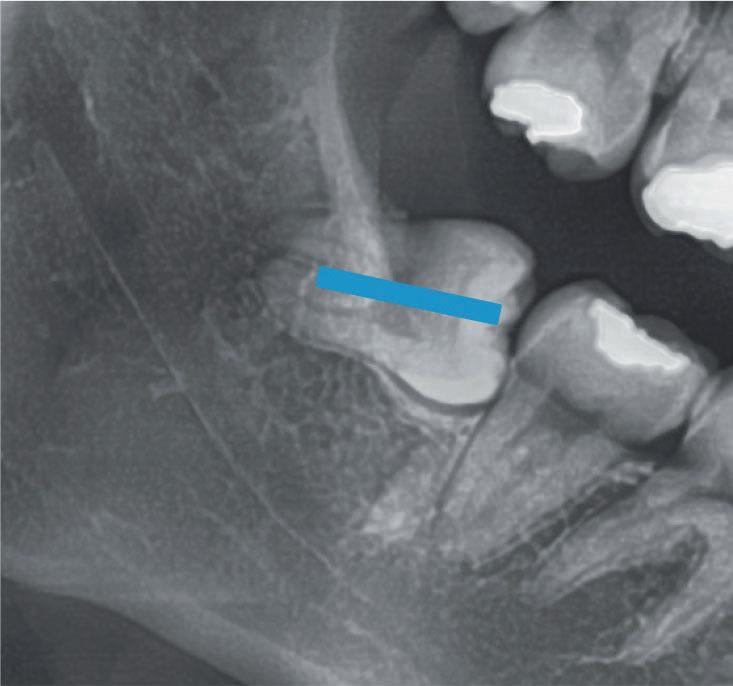

Questo schema illustra la quantità di dente rimosso (sezionamento della corona), l’angolo di accesso e la direzione dell’estrazione del dente. Fig. 139

Il blu indica la quantità di dente rimosso quando esso viene sezionato orizzontalmente, mentre il rosso quando è sezionato verticalmente.

Fig. 139 - Questo schema illustra la quantità di dente rimosso (sezionamento della corona), l'angolo di accesso e la direzione dell'estrazione del dente.